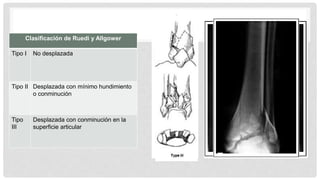

Clasificación de Ruedi y Allgower

Tipo I No desplazada

Tipo II Desplazada con mínimo hundimiento

o conminución

Tipo

III

Desplazada con conminución en la

superficie articular